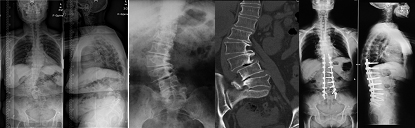

女性,17岁,胸腰段结核性后凸,术前后凸角度130o,经后路矫形术后仅剩37o,矫正率71.5%

男性,48岁,脊柱后凸畸形强直性脊柱炎,术前后凸角度115o,经后路矫形术后仅剩20o,矫正率82.6 %

女性,65岁,成人腰椎侧凸,侧凸角度46o,行侧凸矫形固定、植骨融合,术后侧凸角度减小为5o